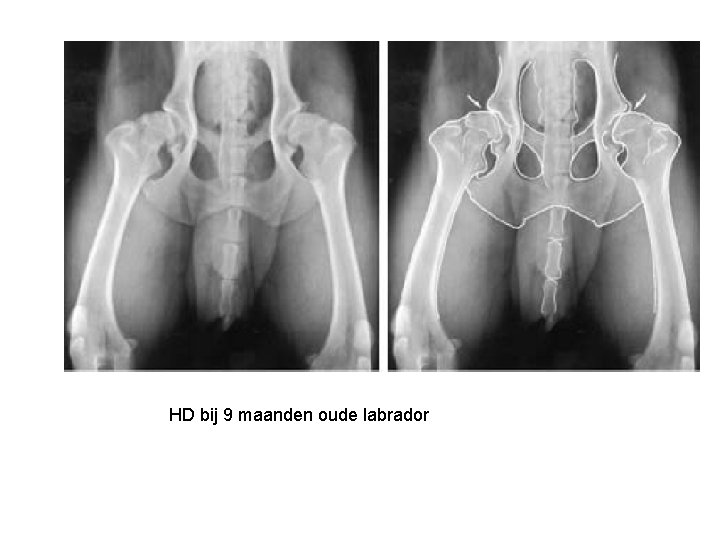

HD bij 9 maanden oude labrador

Heupdysplasie (HD)

Heupdysplasie • Vnl bij grote honden (kat en middelgrote hond) • Heupgewricht is niet goed gevormd: Kom is te ondiep en kop te klein – klein contact opp. degeneratie van het gewr. Kraakbeen – Voortdurende beweging vd kop in de kom Ontstekingsreactie non-septische artritis artrose met botwoekeringen – Gewrichtsbanden te slap (sub)luxatie • Pijn (mate van pijnijkheid hangt niet samen met bevindinge op RX)